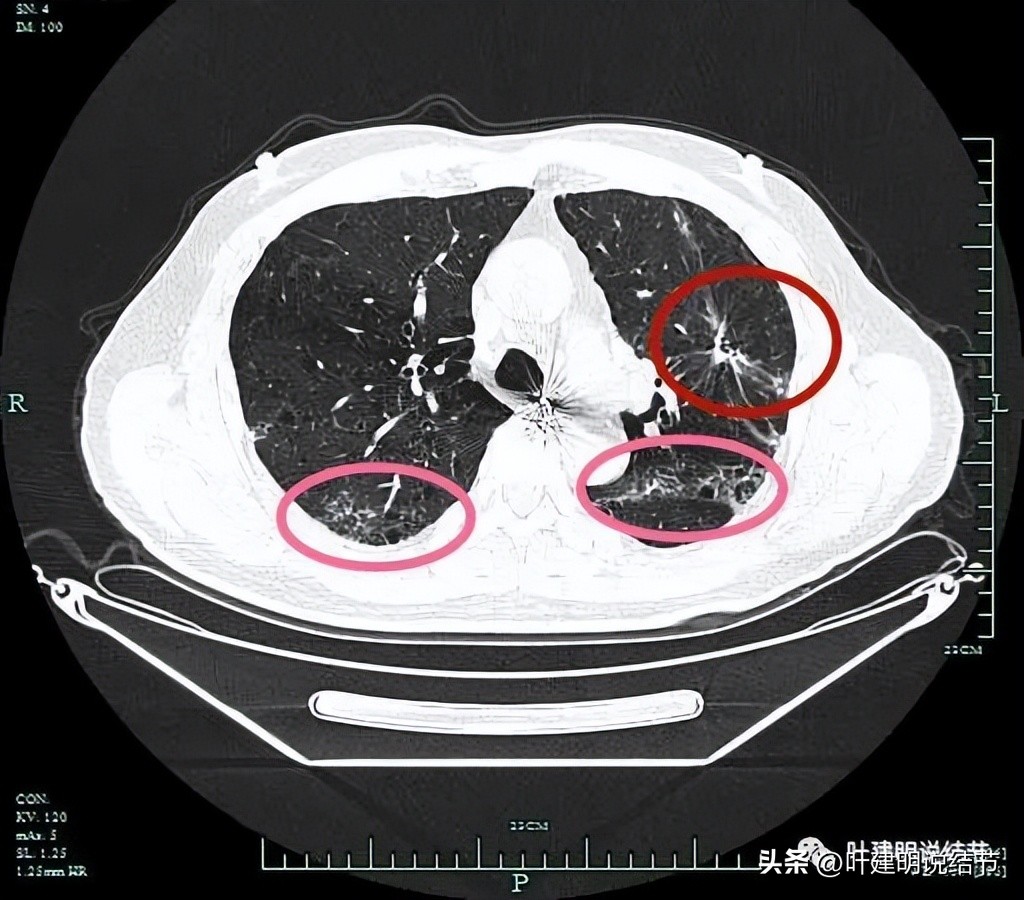

左上病灶开始出现,周围伴慢性炎的表现(红色圈起来部位);其他余部分有多处炎性改变(粉色圈起来的)。

分叶征(砖色箭头);毛刺征(紫色箭头);胸膜牵拉(蓝色箭头);病灶有膨胀感(红色箭头)。

上图层面明显明显的收缩力、分叶、胸膜牵拉以及血管进入(桔色箭头)。

病灶实性,有纠集感;有胸膜牵拉;有毛刺征;有血管征。

余肺多处间质性炎症或新冠后没有吸收的表现。